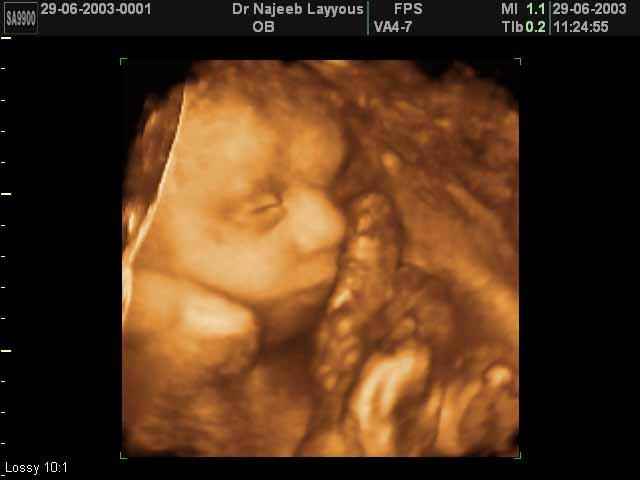

صور جانبية لرأس الجنين بجهاز الالتراساوند ثلاثي الأبعاد | الدكتور نجيب ليوس